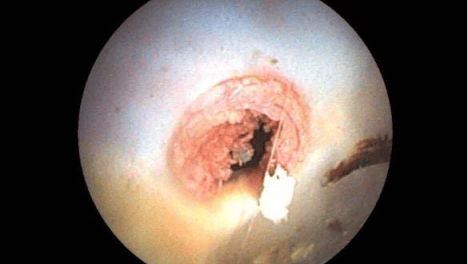

2021年11月4日经右额弧形切口颅骨钻孔,软性内镜下鞍上池囊肿-脑室脑池造瘘,双侧颞极蛛网膜囊肿-基底池造瘘术。(鞍上池囊肿顶壁造瘘后经瘘口所见囊肿底壁及颅底动脉环)电子软性内镜柔软纤细光滑,可以仅通过一个…